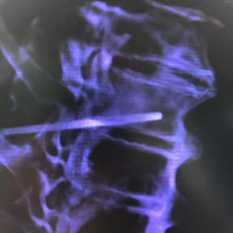

о Кальцификация нервов, считается патогномоничным признаком (редко встречается)

(Справа) Рентгенография в ЗП проекции: выраженный акроостеолизис, большая часть фаланг разрушена. Кроме того, отмечается линейная кальцификация в зоне нерва пальца. Эта комбинация признаков патогномонична для лепры.